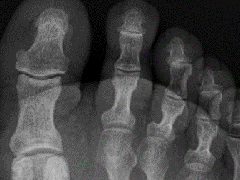

• lisfranc损伤2例X线影像

lisfranc损伤2例X线影像